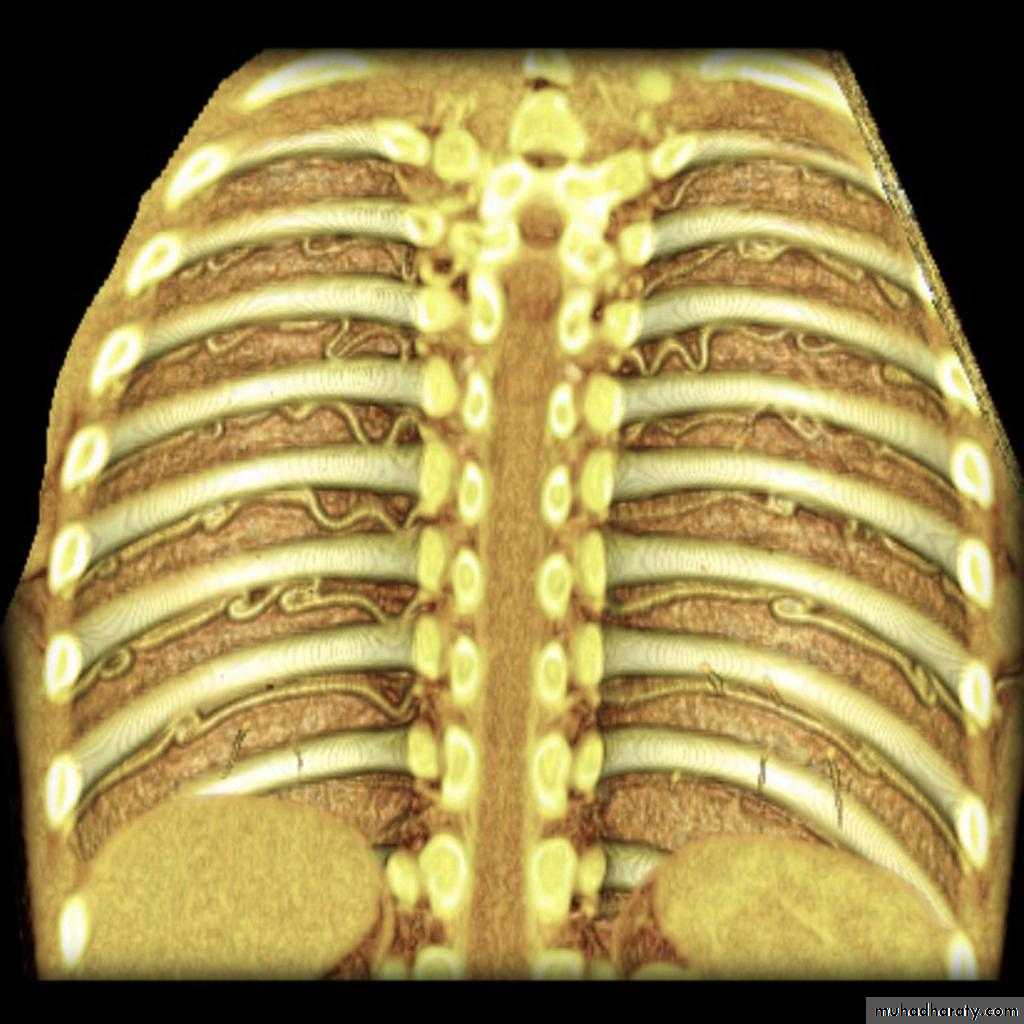

Coarctation of the Aorta: Investigations

CXR:Rib notching: from enlarged collaterals

Prestenotic and post-stenotic dilatation form the “3 sign” of the descending aorta

Echocardiography:Shows the site of stenosis & pressure gradient across it

CT & MRI: can show the entire extent of the aorta